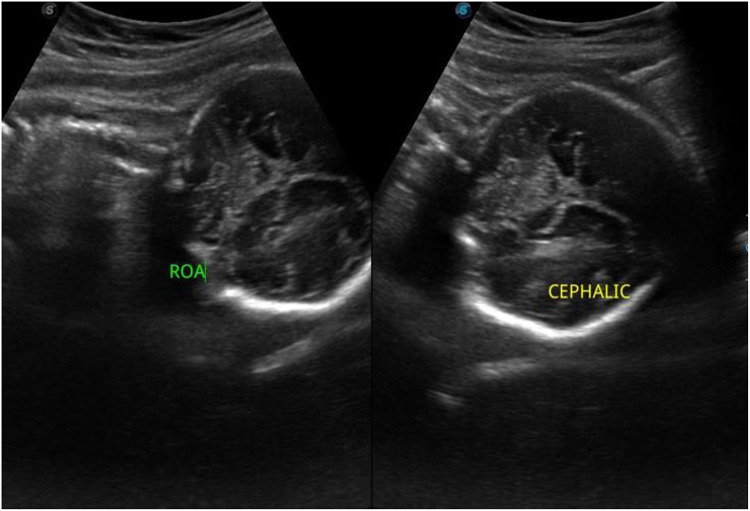

Case presentation: We report the case of a 30-year-old woman at 33 weeks of gestation who presented with right lower quadrant pain initially misattributed to round ligament strain. Her condition deteriorated over several days with worsening abdominal pain, fever, and leukocytosis. Imaging confirmed an acute uncomplicated appendicitis. After multidisciplinary evaluation and counseling, the patient declined surgery due to concerns over fetal safety. A conservative approach with intravenous antibiotics was initiated, resulting in complete clinical resolution. The patient delivered a healthy infant at term, without complications or recurrence.